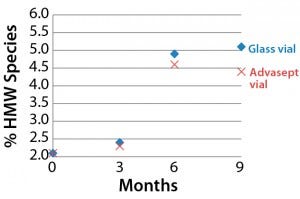

SEC Analysis: All SEC data (pre- and postfill, and upon storage) show comparable percentages of high–molecular-weight (HMW) species for both the glass and Advasept vials (Figures 2–4).

Figure 4: Percentage of high–molecularweight

species detected over time (5 °C)